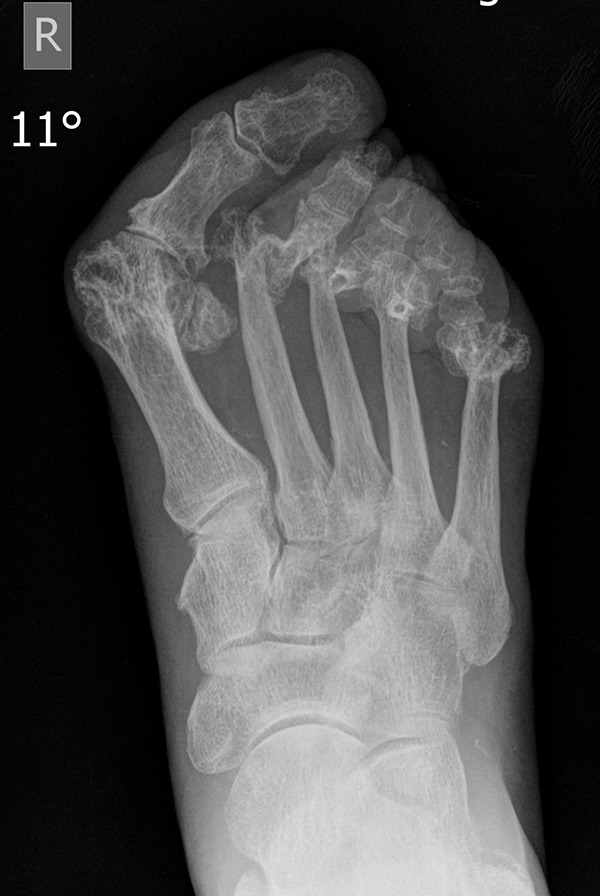

Nach Anamnese und Untersuchung reichen meist konventionelle Röntgenbilder mit Belastung im Stehen a.p. und seitlich ggf. Schrägaufnahmen zur Beurteilung und Indikationsstellung aus. CT oder MRT sind in der Regel nicht erforderlich, im Einzelfall aber ergänzend sinnvoll. Szintigraphie und Sonographie spielen bei der Indikationsstellung und Operationsplanung eine untergeordnete Rolle.